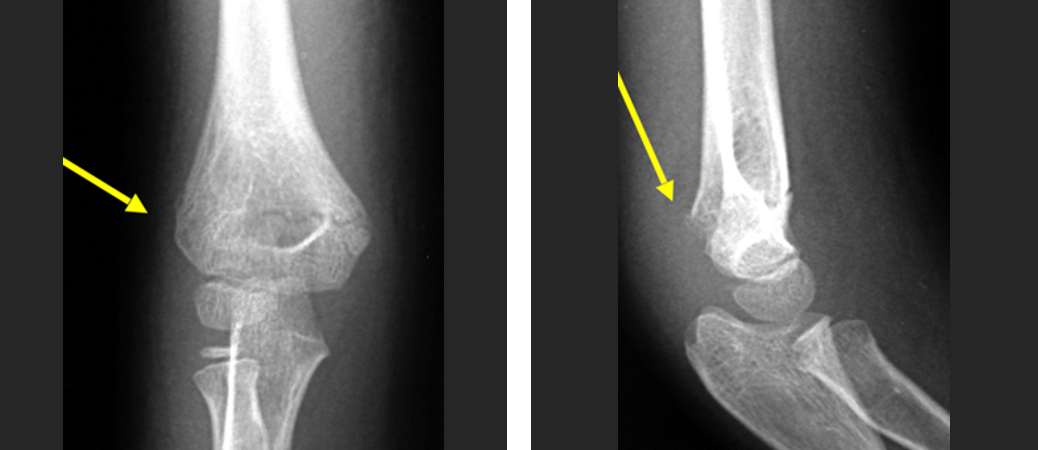

肘关节骨折脱位 我们该如何正确诊治 好医术早读文章 好医术 赋能医生守护生命

子どもが肘を骨折して手術。 治療期間はどのくらいだった? 18年12月2日 / 19年2月1日 スポンサーリンク 子供が肘を骨折し、手術しました。 肘の完治までどのようなスケ電話予約可 肘頭骨折、尺骨近位端骨折 肘の骨折です。 肘の後ろに出っ張っている骨を肘頭をいいます。 この骨には肘を伸ばすための上腕三頭筋がついています。 また肘関節内の病因 播报 本病由直接外力引起的骨折很少见。 常见的是肘关节伸直位摔倒,手掌着地,外力使桡骨头在外翻位与肱骨小头撞击而产生骨折。 常合并肱骨小头损伤与内侧副韧带损伤。 多见于成年人且容

骨折の治癒過程は炎症期、修復期、改変期(再造形期)の3ステージに分類されます。 それでは一つ一つのステージやかかる期間について解説していきます。 炎症期 骨折が起きると骨 以下は、70代女性の肘の骨折の受傷時のレントゲンです。 転位が大きく、手術を行いました。 術後のレントゲンです。 正常な位置に整復されている事がわかると思います。 手術翌日よ